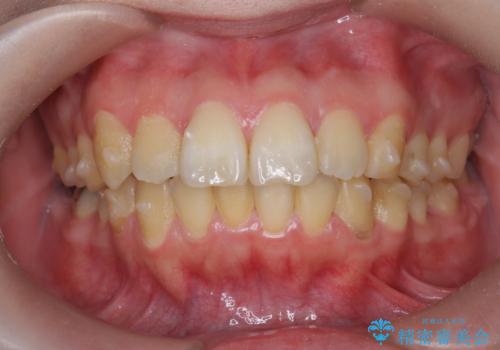

歯を抜かずに行う前歯の角度の改善

- 歯を抜かずに前歯の角度を改善したい、と矯正治療を希望され来院されました。

可及的に前歯部にIPR(歯間の削合)を行い、抜歯をせずマウスピース矯正システムインビザラインで歯の排列を行っていく治療計画としました。

治療の前後を比べると、がたつきや歯の角度が改善したことがしっかりと確認されました。